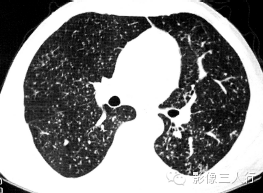

| 病毒性肺炎(图1) | 粟粒性肺结核(图2) | 细支气管肺泡癌(图3) | 肺尘埃沉着病(图4) | 肺泡蛋白沉着症(图5) | 血吸虫病(图6) | |

散在分布,6〜8mm或更小 | 分布均匀,直径1〜2mm | 分布不均,直径6〜7 mm | 分布不均,直径多为2〜5mm | 地图样、铺路石征 | 大小不等,直径多为1〜5mm |

较模糊 | 较清楚或较模糊 | 较清楚 | 较清楚 | 较清楚 | 较模糊 |

病灶密度相同,大小不等 | 病灶密度相同或不同 | 病灶密度相同,呈含气支气管征及蜂窝征 | 病灶密度不均,有钙化 | 磨玻璃密度,地图样分布和铺路石征 | 病灶密度不均,典型者可见晕征 |